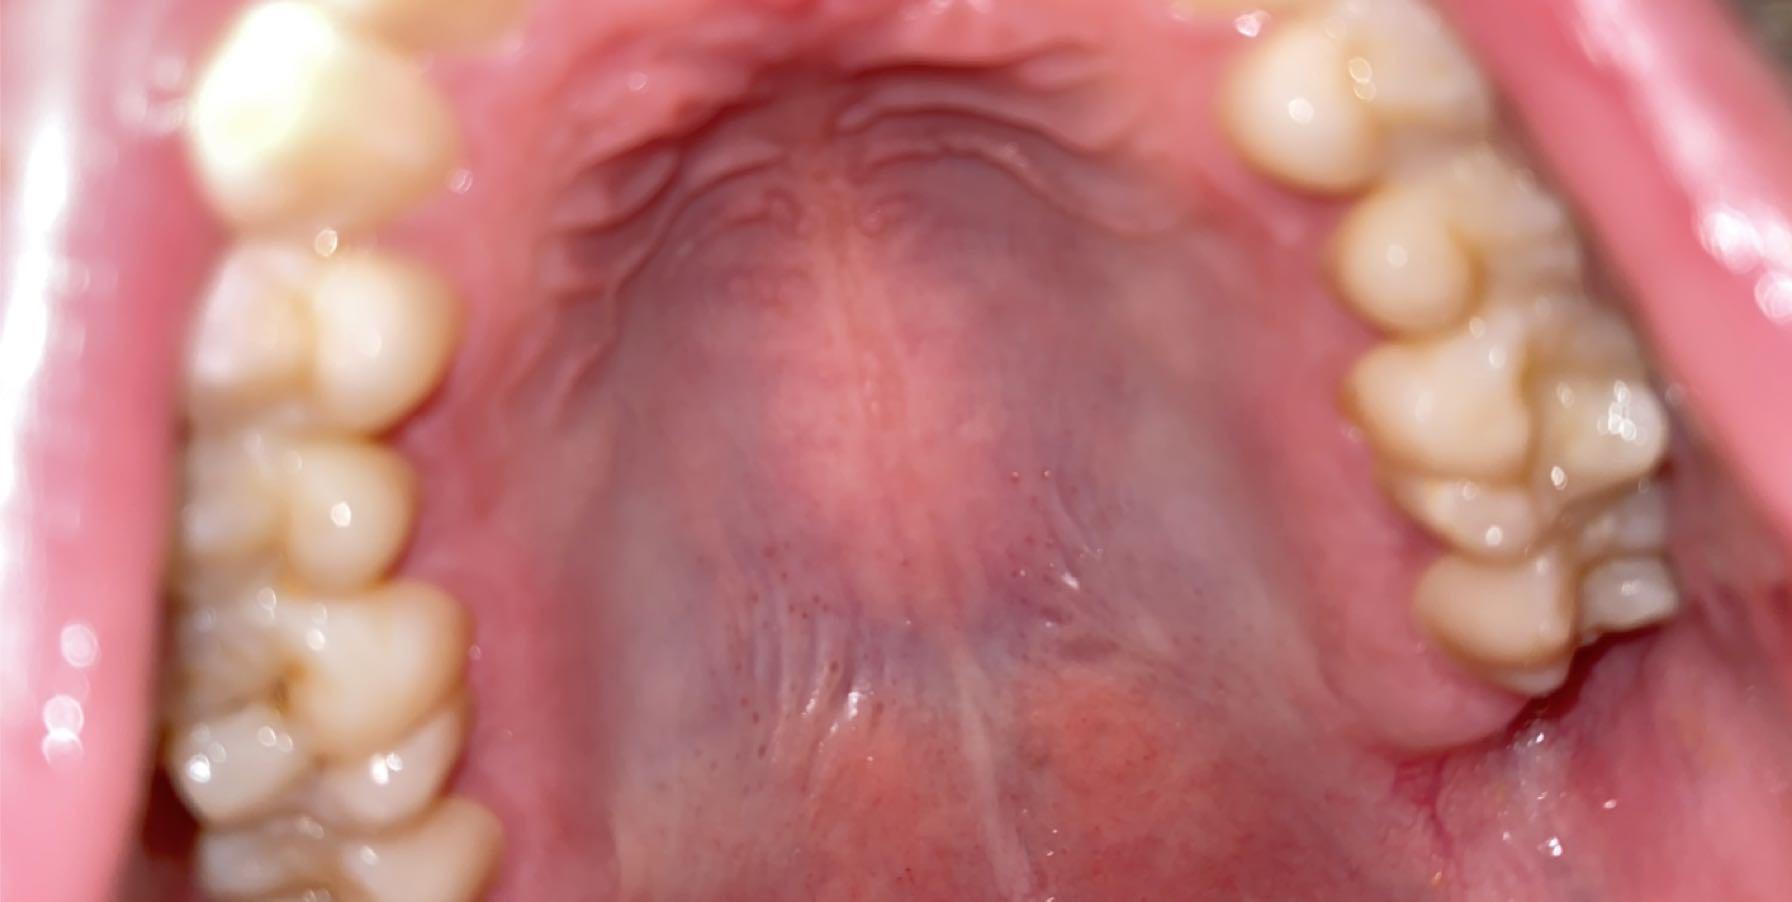

What are these black dots on the roof of my mouth. My throat also hurts Black Dots On Back Of Throat Tonsillitis can feel like a bad cold or flu. The tonsils at the sides of your throat will be red and swollen. Epiglottitis is inflammation and swelling of the epiglottis. Signs and symptoms of tonsillitis include swollen. You can tell the primary symptom of cobblestone throat by its name — bumps in the back of your throat that resemble cobblestones.. Black Dots On Back Of Throat.